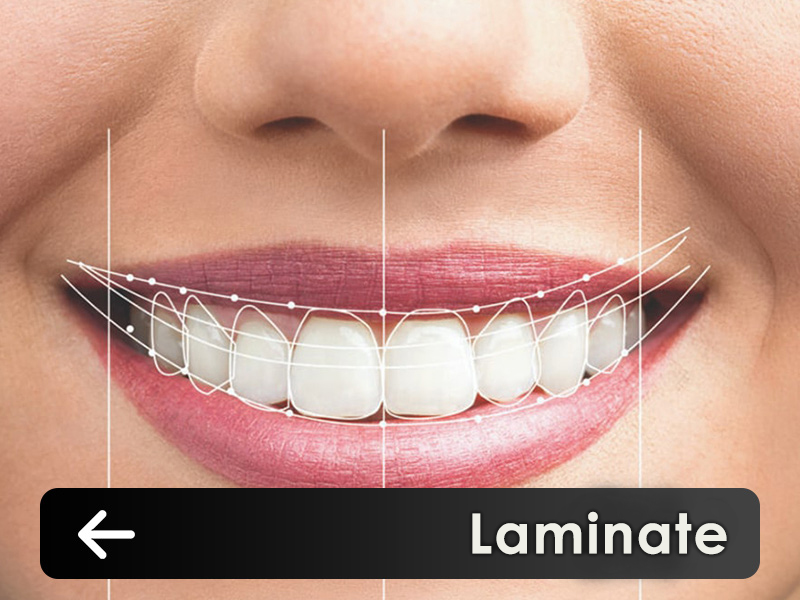

services

The set of digital laboratories of Ganjineh Teb Arman Company provides a complete set of stages from the treatment plan to the manufacture of therapeutic aids and prosthetics by using the skills of experienced technicians and expert dentists..Login and register in the system